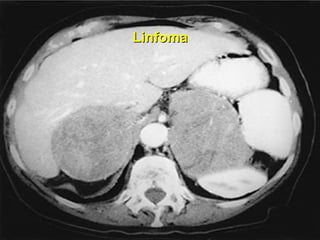

Linfoma

TUMORES METASTÁTICOS 6 – 38 % Mama Pulmão Rim Linfomas Melanomas História prévia tumores Lucon AM, Latronico AC. Doenças benignas e malignas das supra-renais. In: Barata HS, Carvalhal GF. Urologia - Princípios e Prática. Pp. 581-7, ed. ArtMed. 1999

TUMORES METASTÁTICOS 6– 38 % Mama Pulmão Rim Linfomas Melanomas História prévia tumores Lucon AM, Latronico AC. Doenças benignas e malignas das supra-renais. In: Barata HS, Carvalhal GF. Urologia - Princípios e Prática. Pp. 581-7, ed. ArtMed. 1999